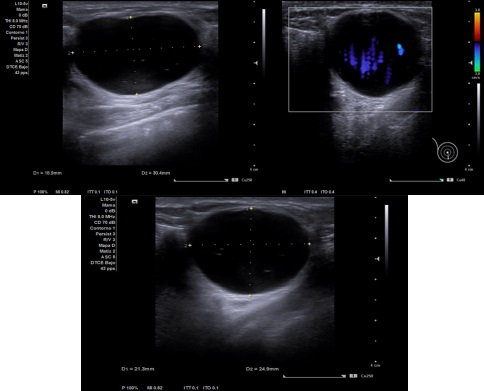

Caso 3: Lesión en zona superior central a la areola, ecoestructura de limites irregulares e hipoecogénica, microcalcificaciones de 12 x 12 aproximadamente, no captación de Doppler.

Caso 3: Biopsia + PAAF de radiodiagnóstico de adenopatía axilar derecha, hallazgos citológicos positivos para células neoplásicas, compatibles con una metástasis ganglionar de un carcinoma de probable origen mamario.

Caso 3: Adenocarcinoma mamario.

Diagnóstico diferencial: Tumoración benigna de mama.

Caso 3: quimioterapia neoadyuvante por 6 meses y luego intervención quirúrgica.

En el Caso 3 la paciente recibiendo quimioterapia y en el resto no ha sido requerido seguimiento.